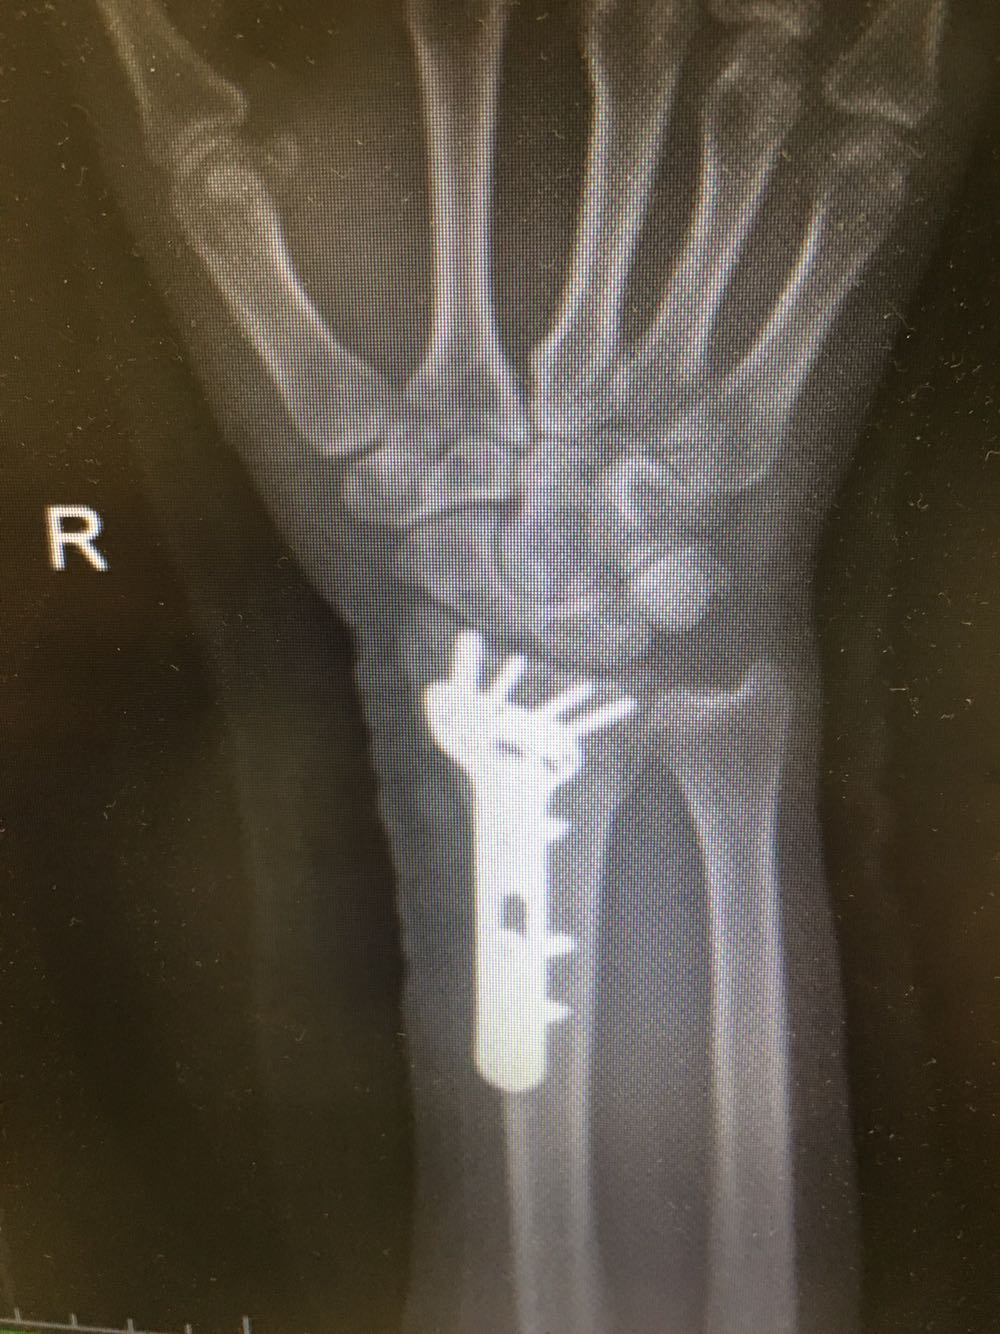

患者,女性,62岁 主诉:外伤致右腕部疼痛伴活动受限8小时 现病史:患者于8小时前受外伤后出现右侧腕部剧烈疼痛,后出现肿胀伴活动障碍,否认头晕头痛、恶心呕吐等不适,遂至我院就诊,查X片示:右侧尺桡骨远端骨折,现为进一步诊治收治入院,发病以来,神清,精神可,胃纳夜眠可,二便无殊,体重无明显变化。

查体:右侧腕部肿胀,压痛阳性,伴活动受限,远端肢体感觉及运动正常。 辅检:见现病史

诊断:右侧尺桡骨远端骨折 治疗:完善术前检查后行手术内固定